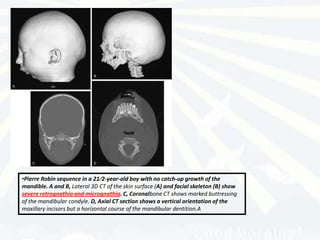

•Pierre Robin sequence in a 21⁄2-year-old boy with no catch-up growth of the

mandible. A and B, Lateral 3D CT of the skin surface (A) and facial skeleton (B) show

severe retrognathia and micrognathia. C, Coronalbone CT shows marked buttressing

of the mandibular condyle. D, Axial CT section shows a vertical orientation of the

maxillary incisors but a horizontal course of the mandibular dentition.A